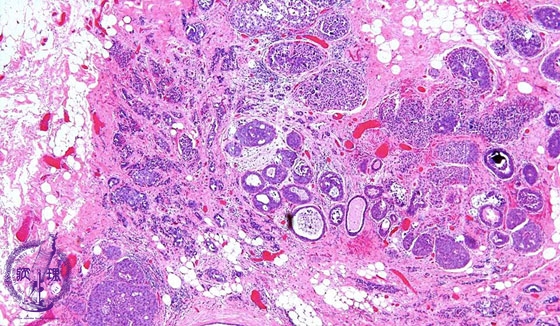

- 14.Breast

- ★(6)Invasive ductal carcinoma(Papillotubular carcinoma)

Microscopic image(HE stain, low power view):An example of well-differentiated type of invasive ductal carcinoma showing duct formation and/or papillary proliferation. In addition to intraductal spread, extensive stromal invasion (dotted line) is also apparent.